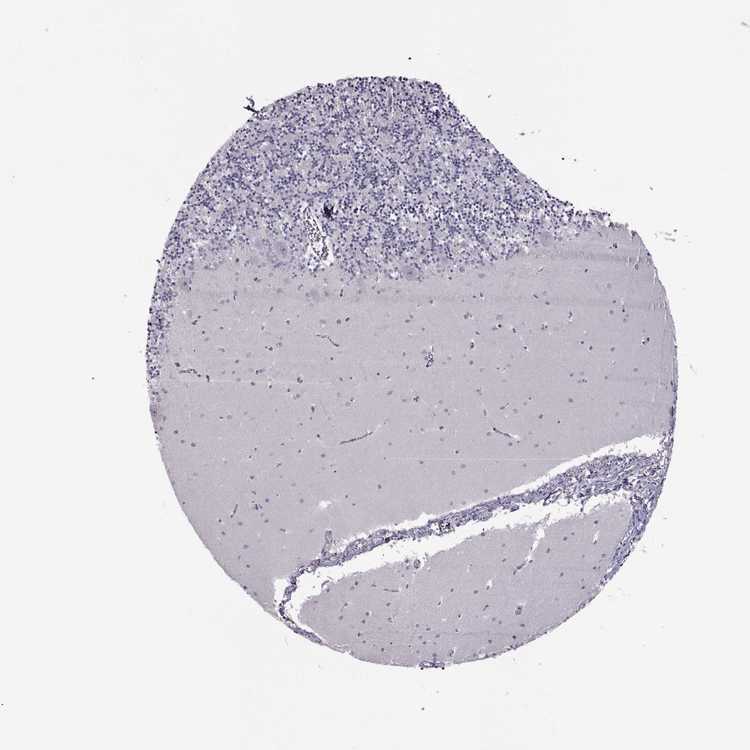

BRAIN CEREBELLUM Show tissue menu

CEREBELLUM - Expression summary

CEREBELLUM - Antibody stainingi

Antibody staining in the annotated cell types in the current human tissue is reported as not detected, low, medium, or high, based on conventional immunohistochemistry profiling in selected tissues. This score is based on the combination of the staining intensity and fraction of stained cells.

Each image is clickable and will lead to virtual microscopy that enables deeper exploration of all samples and also displays staining intensity scores, fraction scores and subcellular localization as well as patient and tissue information for each sample.

Antibody HPA042710Antibody HPA071119

Purkinje cells Not detectedNot detected

Cells in granular layer Not detectedNot detected

Cells in molecular layer Not detectedNot detected